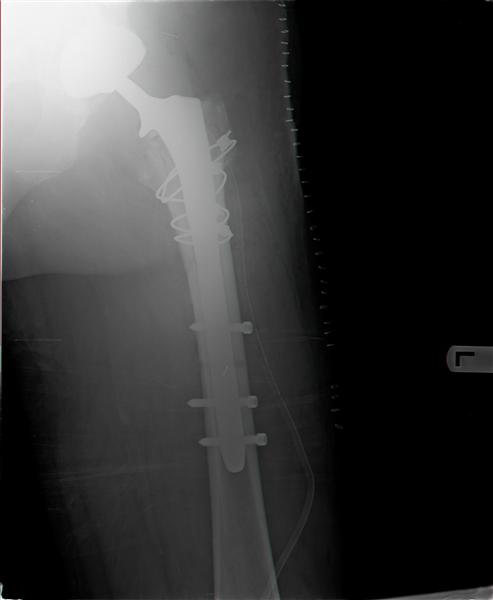

Michael Markushevich 18 Октябрь 2007, 02:29

Good evening!In the morning operation was done.

Procedure was much more difficult that my sense.

Socket is acceptable position so wasn't change.Fracture proximal femur - three part I mean G.T & L.T. After removal femoral prosthesis was done reduction of L.T & Calca. Reaming and insert new prosthesis with distal locking by 3 screws,reduction G.T.and fixation by 4 cyrclages.

Connection head and reduction femur.In the end surgery got stable joint.

Here x-ray after operation.